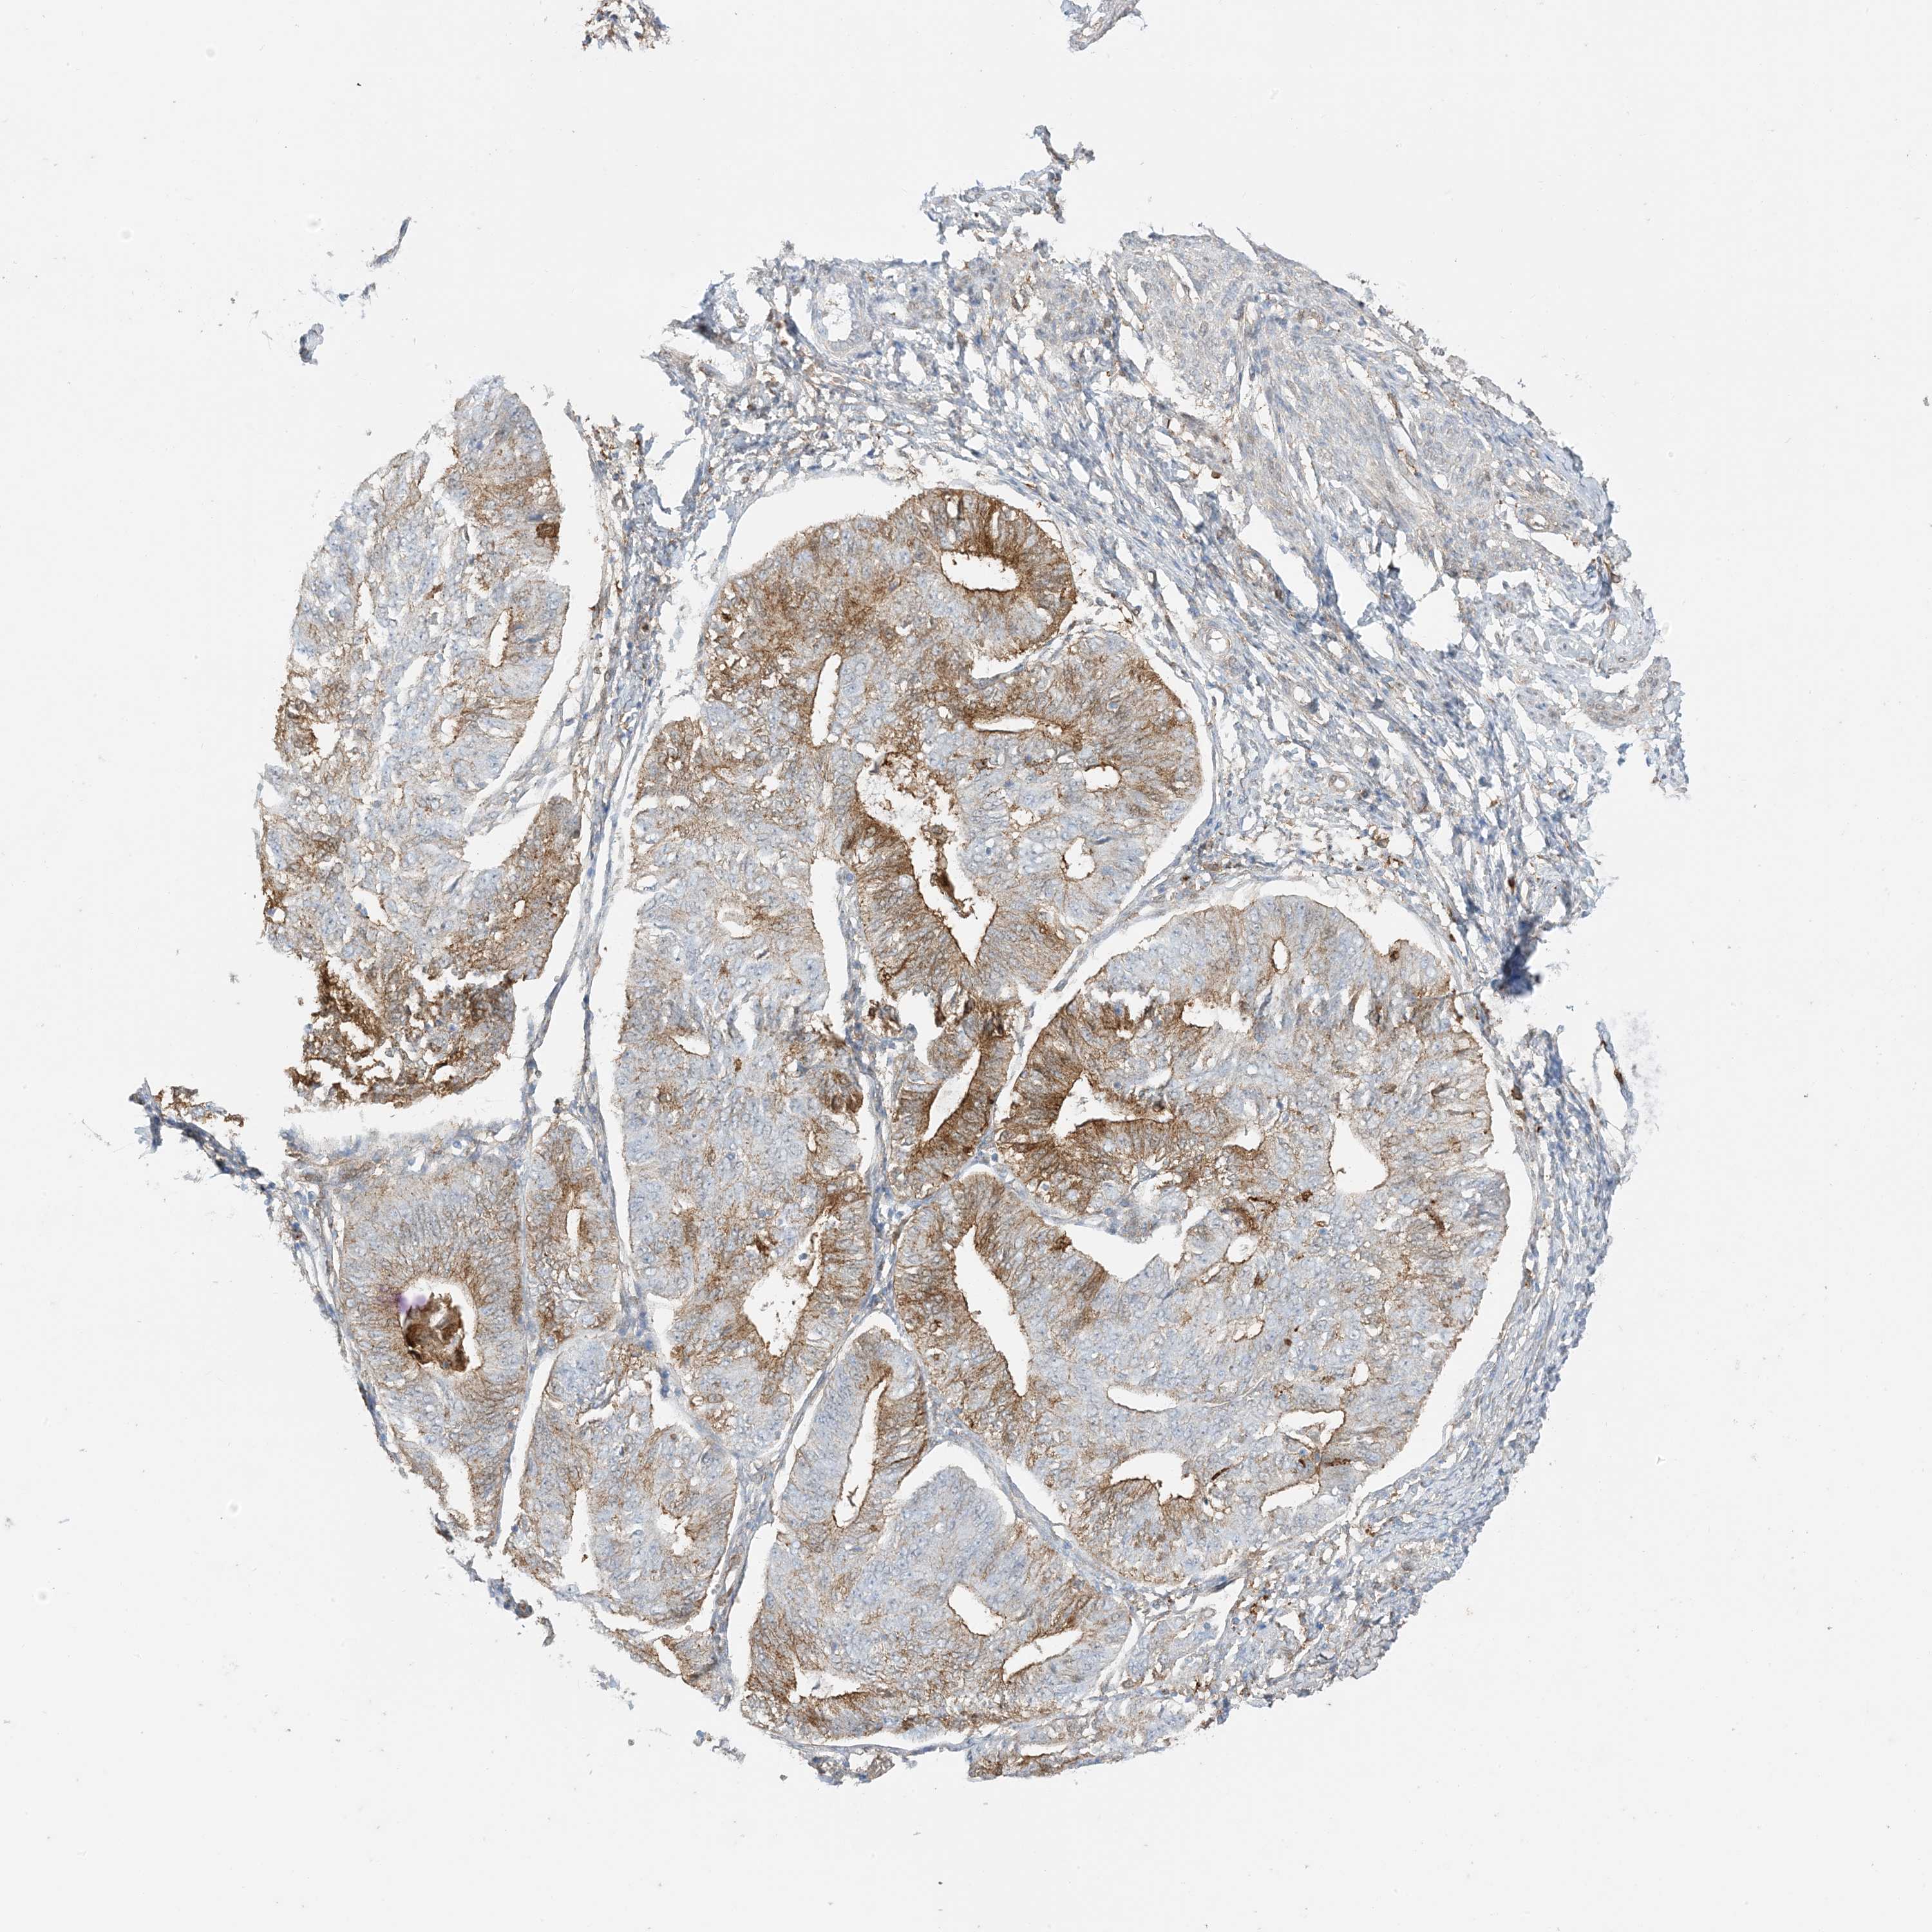

ENDOMETRIAL CANCER - Protein expressioni

A mouse-over function shows sample information and annotation data. Click on an image to view it in a full screen mode. Samples can be filtered based on level of antibody staining by selecting one or several of the following categories: high, medium, low and not detected. The assay and annotation is described here.

Note that samples used for immunohistochemistry by the Human Protein Atlas do not correspond to samples in the TCGA dataset.

Antibody stainingi

Antibody staining in the annotated cell types in the current human tissue is reported as not detected, low, medium, or high, based on conventional immunohistochemistry profiling in selected tissues. This score is based on the combination of the staining intensity and fraction of stained cells.

Each image is clickable and will lead to virtual microscopy that enables deeper exploration of all samples and also displays staining intensity scores, fraction scores and subcellular localization as well as patient and tissue information for each sample.

Antibody HPA054026

Antibody CAB010823

Antibody CAB016728

Antibody CAB036009

Staining

High

Medium

Low

Not detected

Intensity

Strong

Moderate

Weak

Negative

Quantity

>75%

75%-25%

<25%

None

Location

Nuclear

Cytoplasmic/membranous

Cytoplasmic/membranous,nuclear

Adenocarcinoma, NOS

Adenocarcinoma, metastatic, NOS